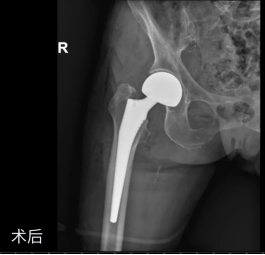

近日,我院骨科在南方医科大学附属第三医院(广东省骨科医院)派驻专家、骨科学科带头人胡舒主任的指导下,以不放弃的医者初心和精准的微创技术,成功

为82岁的中度阿尔茨海默病患者刘奶奶(化名)实施人工股骨头置换术

,不仅精准治疗骨折,更以最小创伤降低术后关节脱位风险,为她留住了早期下床、回归熟悉生活的希望。

2.制定“个性化治疗方案”

在胡舒主任的带领下,骨科团队根据多学科会诊意见,制定精神方面的围术期用药方案以控制精神症状,同时采用单次腰麻以减少麻醉药物对大脑的刺激。术中通过多方面技术调整以缩短手术时间,且最大程度降低脱位风险,既采用微创切口,

不松解梨状肌显露,保留关节囊,适当调整股骨前倾角以及恢复下肢软组织张力等

,最终在术中测试了相对极端动作仍不会脱位的情况下结束手术。